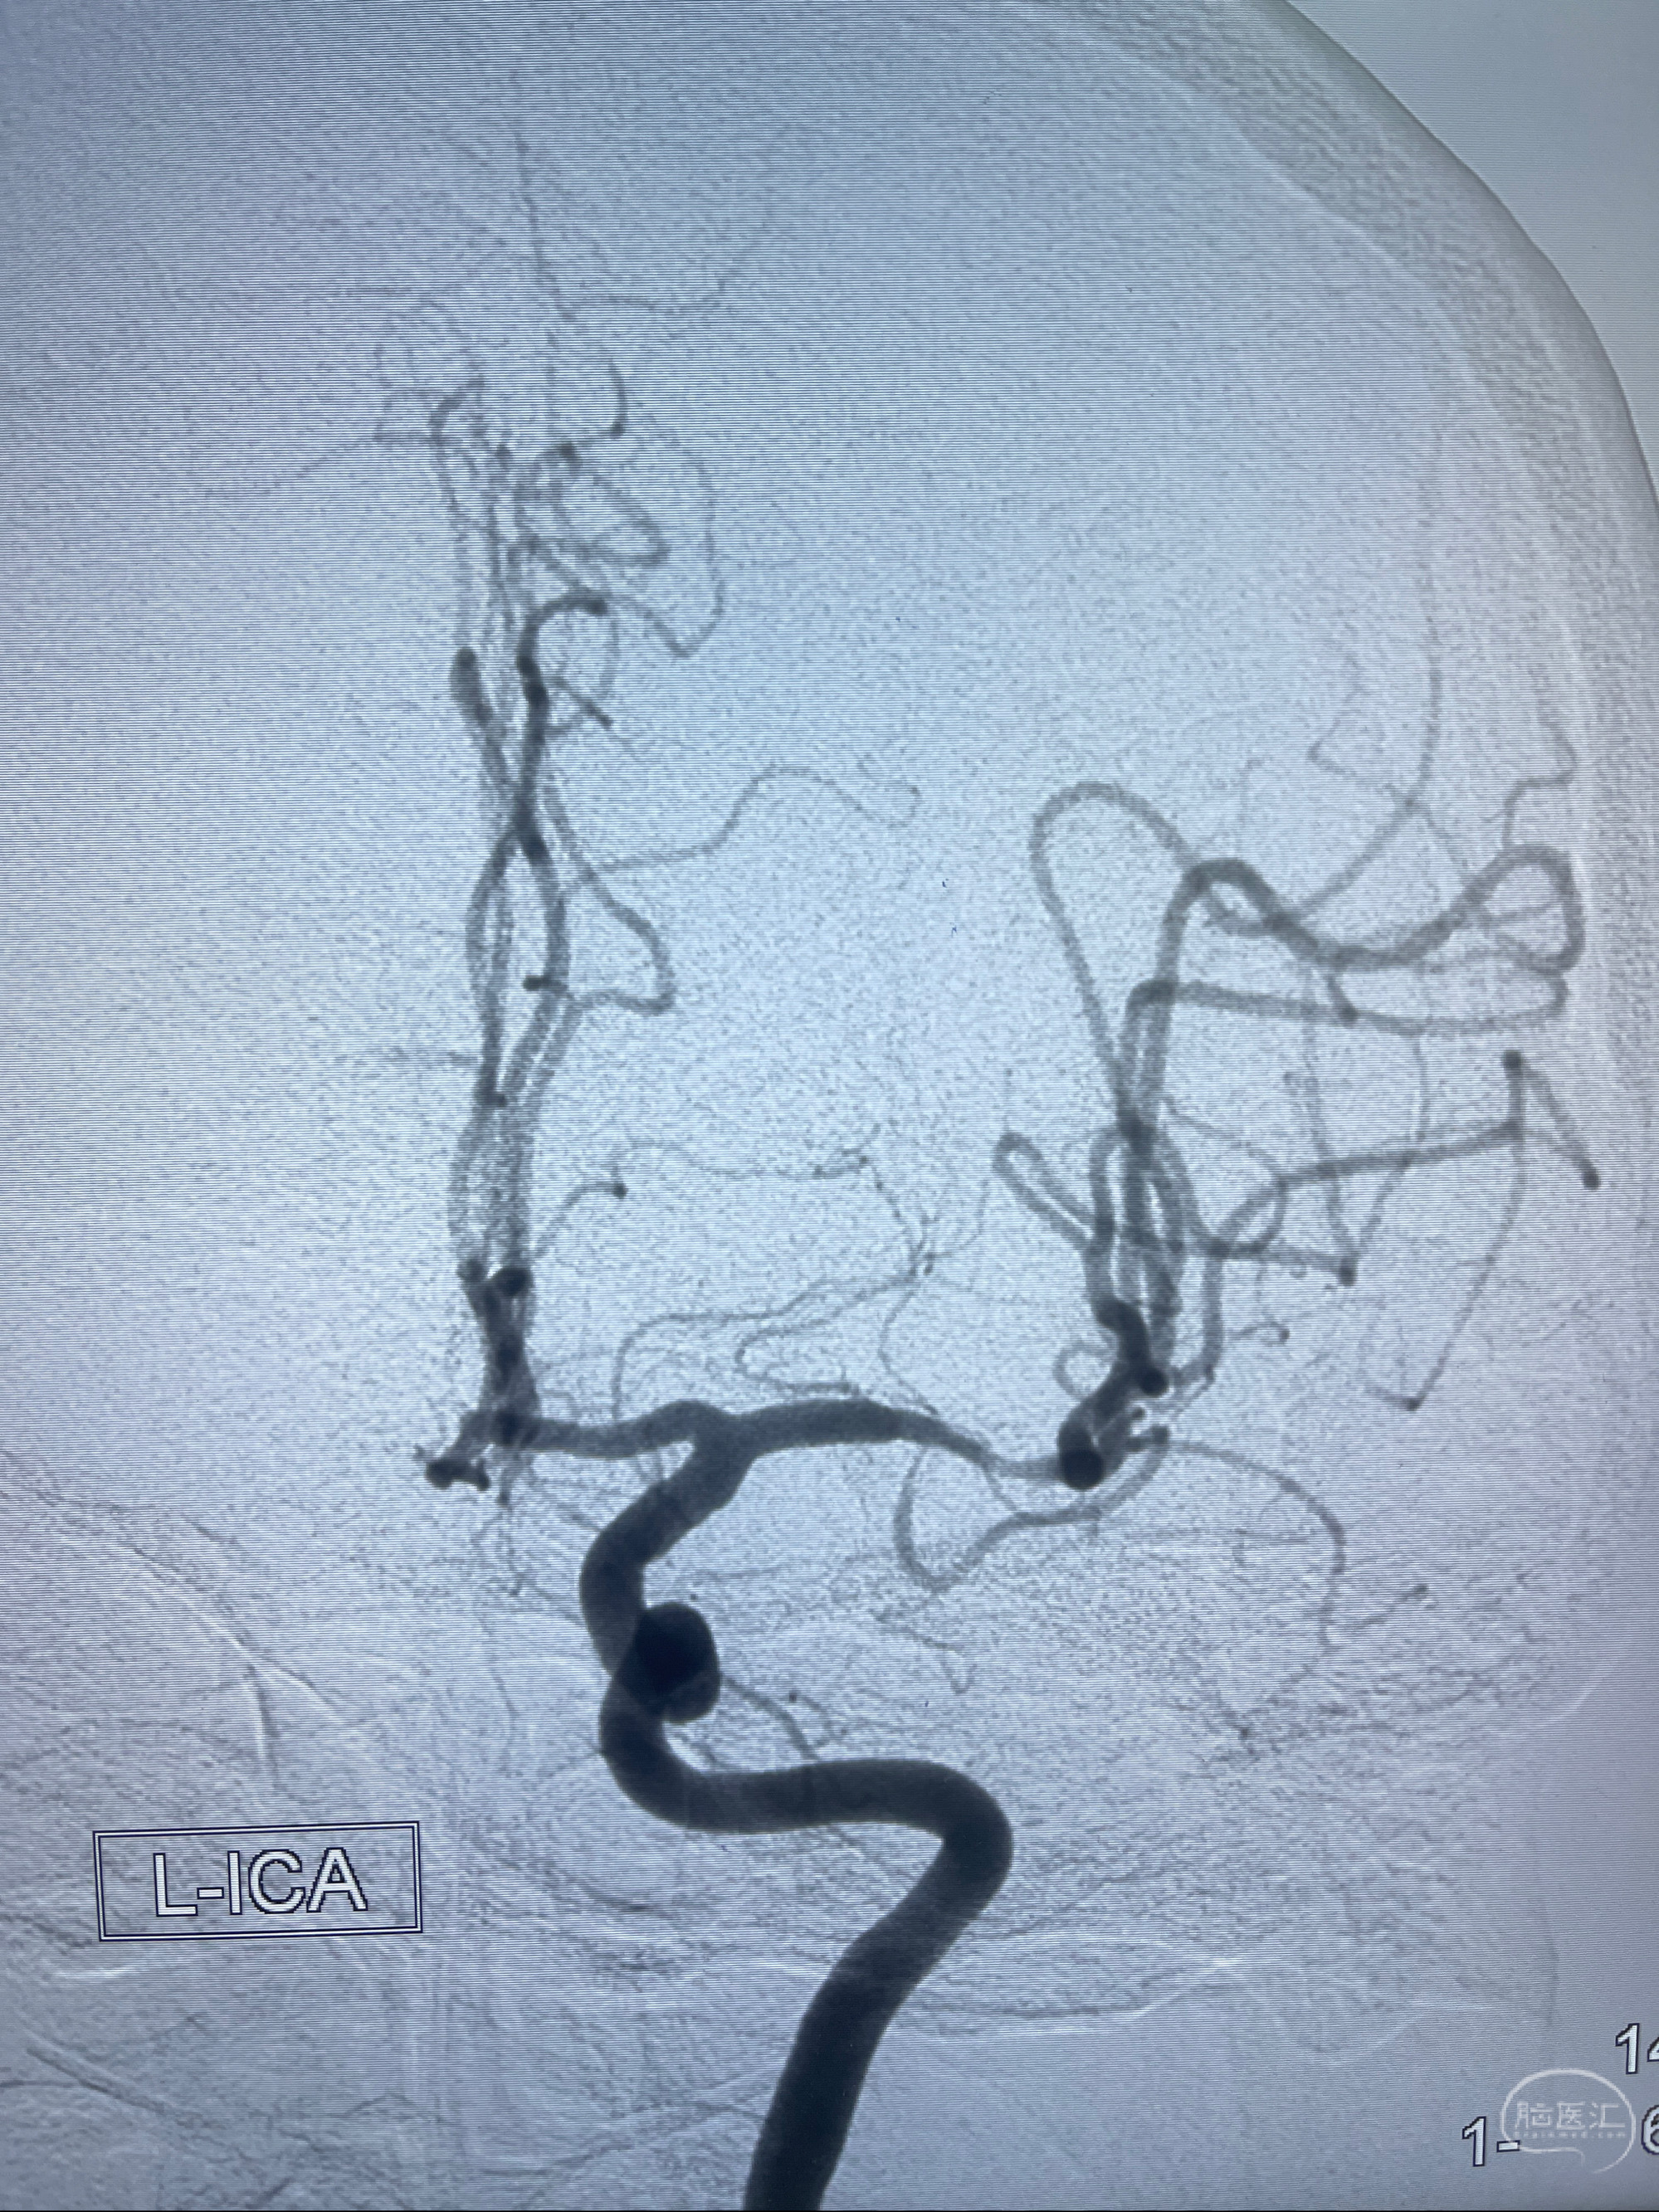

2023-02-02 沛县人民医院 头颅CTA:大脑动脉环发育变异,头颈部动脉粥样硬化,双侧颈内动脉及椎动脉颅内段多发狭窄;

2023-02-15DSA